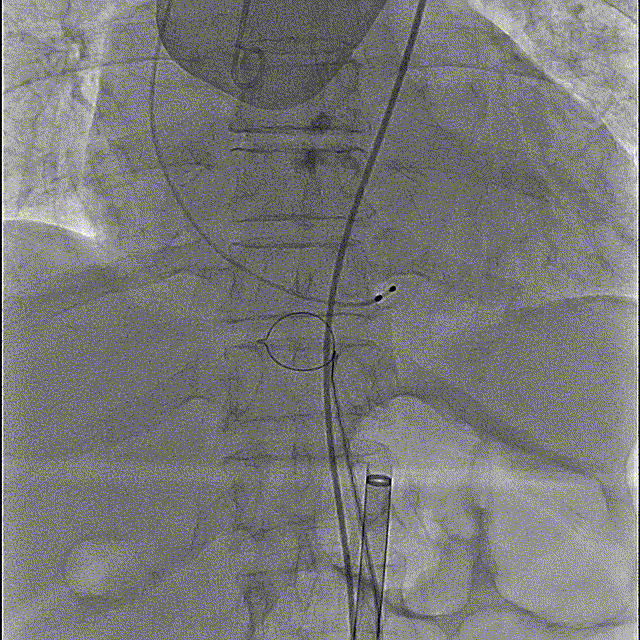

最终释放,瓣架稳定脱钩

释放后造影,可见微量反流

未见明显反流

术后即刻压差从81mmHg下降至23.9mmHg

最终造影

主动脉弓剪影,瓣膜植入深度3mm,冠脉显影正常,主动脉弓正常